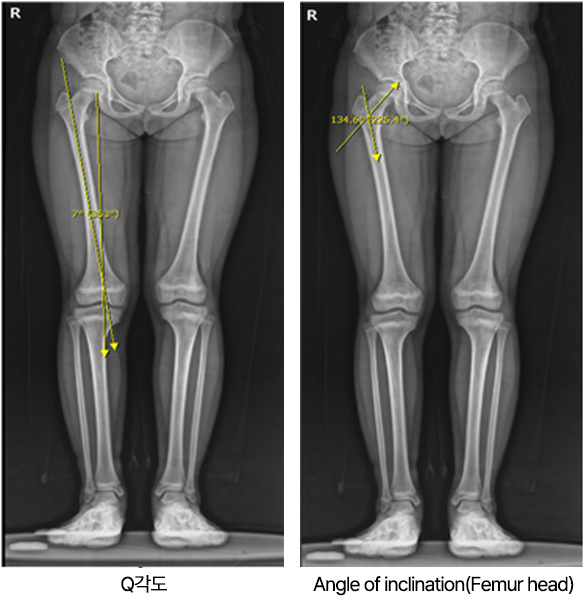

아킬레스 짦음증이 있는 아이들은 자주 발목이나 종아리가 아프다고 하며, 아픈 부위를 특정하지 못하고 다리가 아프다고 하며 내원합니다. 가끔은 발 뒤꿈치를 들고 걷는다고 하거나 까치발로 걷는다고 내원하기도 합니다. 걷는 자세는 주로 팔자걸음에 상체를 흔들면서 걷습니다. 이런 아이들은 좀 더 크면 무릎이나 허리를 아파하기도 합니다. 어린아이들의 경우에는 X-ray 등에도 이상 소견이 보이지 않아 주로 성장통이라고 오진을 받기도 합니다. 저희 병원에서는 현재 이에 대한 연구를 진행하고 있으며, 이런 아이들의 대략 60% 정도에서 비만이 있고, 이러한 비만아이들은 골연령이 약 1.5세 정도 증가하게 되어 성인예측키에서 약 3~4cm 정도의 손실이 발생합니다. (이상은 본원에서의 미발표 연구결과입니다)